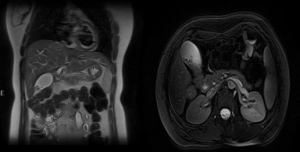

SORU: Sağ üst kadran ağrısı ile başvuran hastanın üst batın MR’ı görülmektedir.

Bu hastada en olası tanı aşağıdakilerden hangisidir?